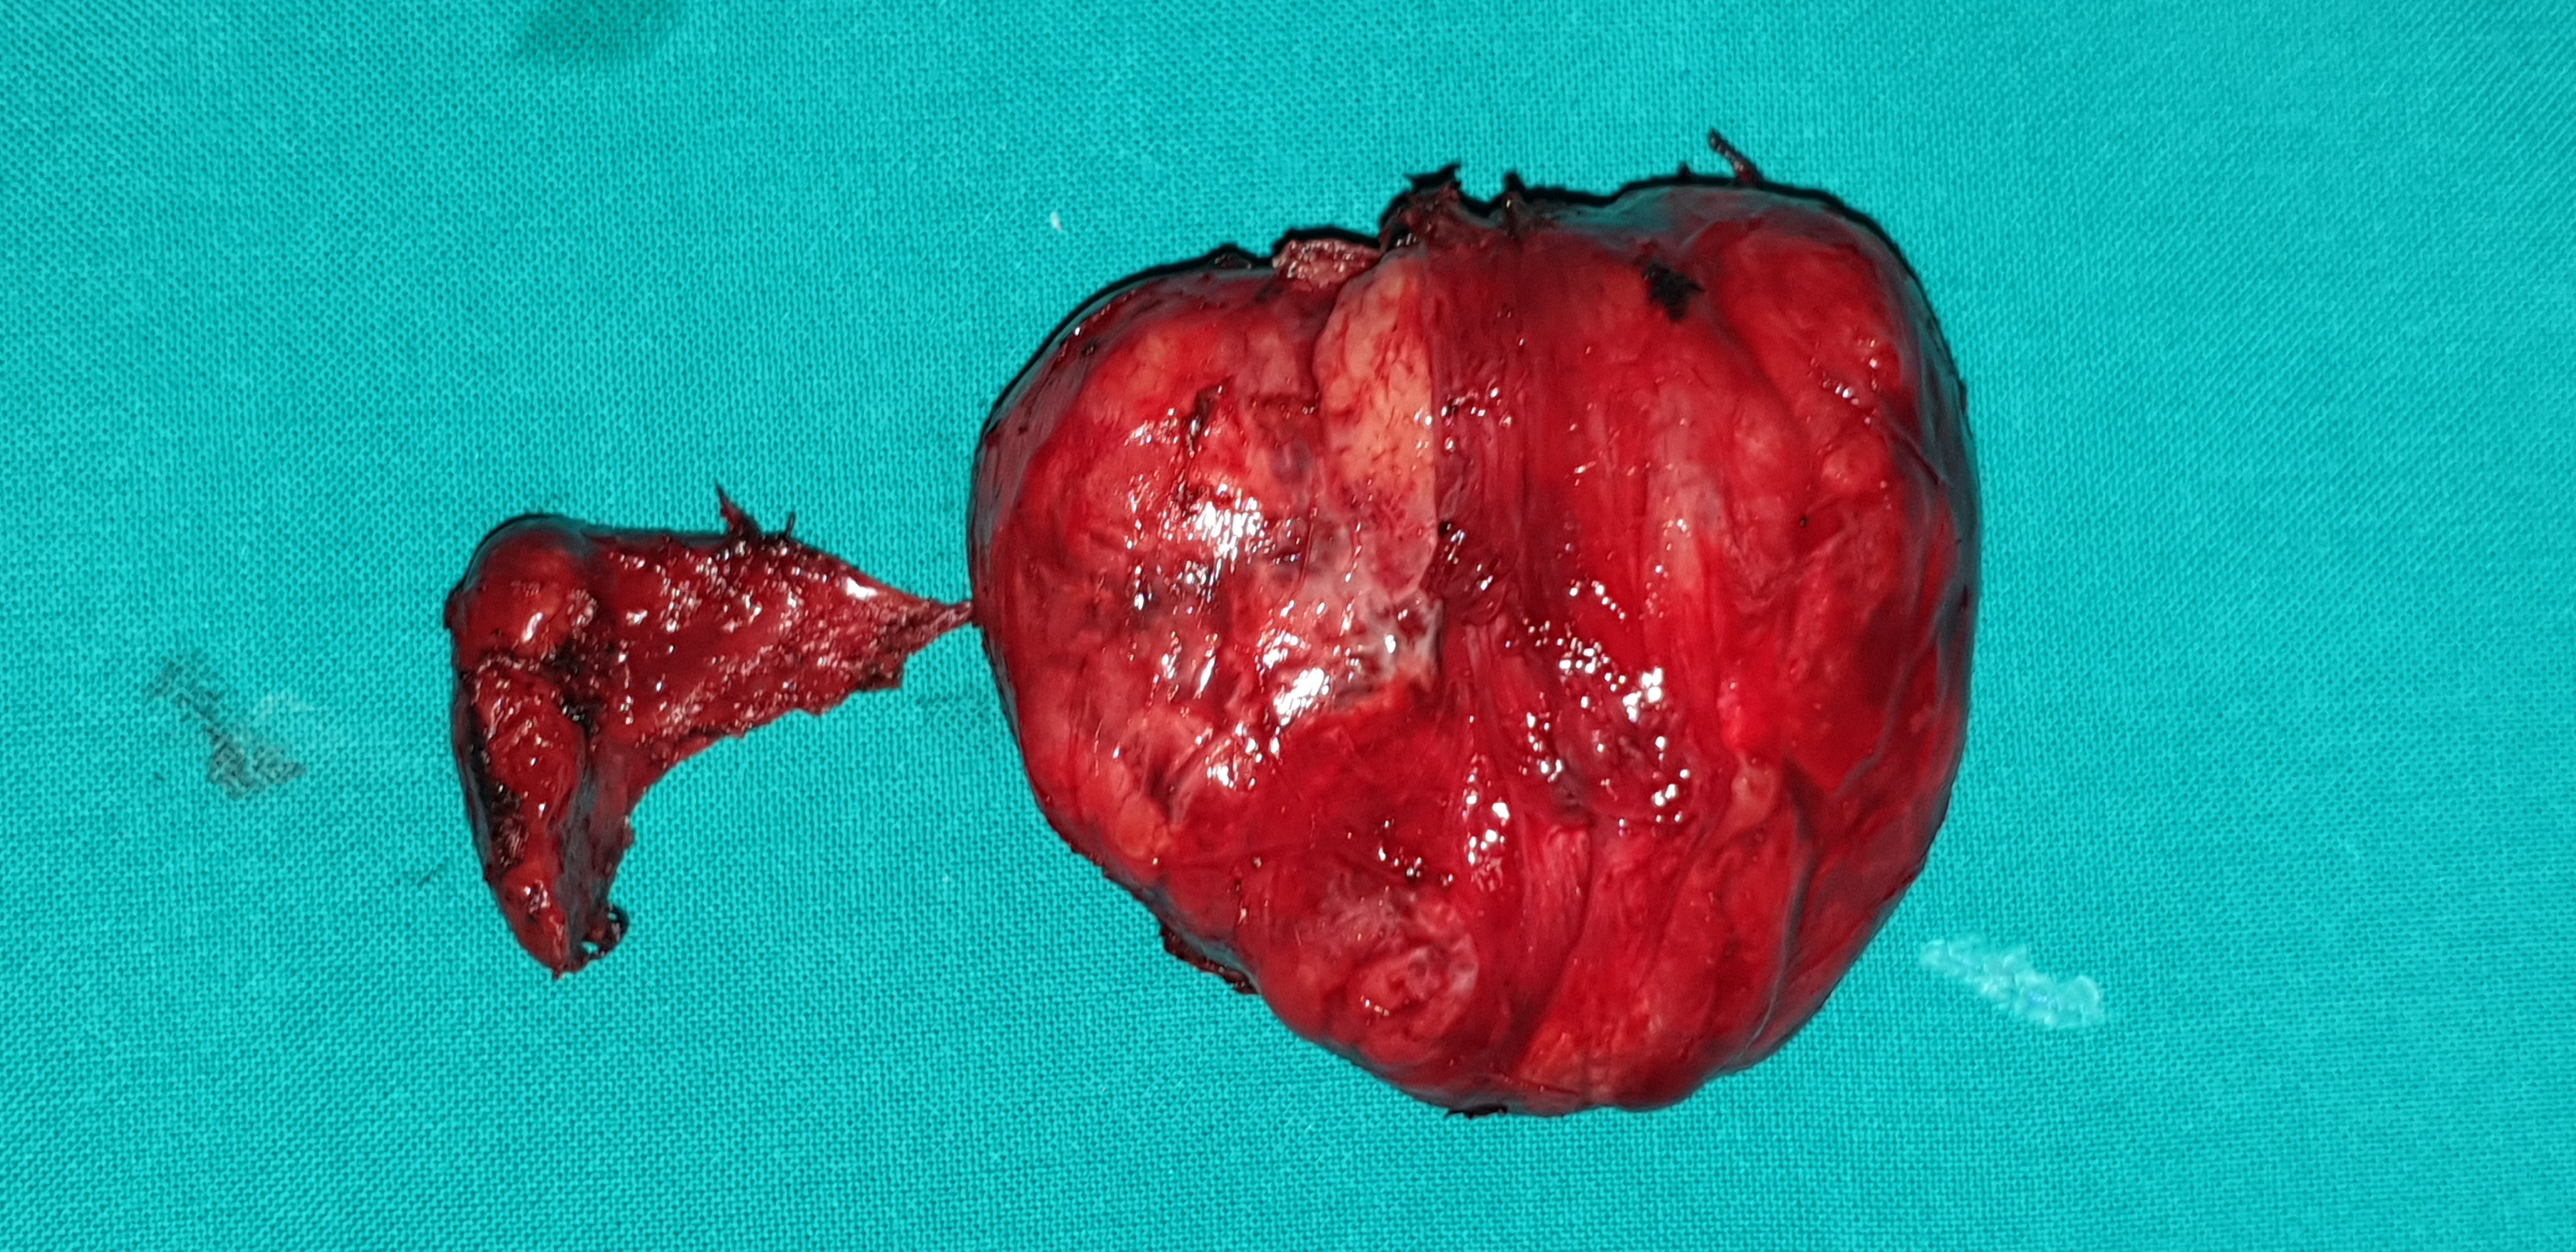

Appearance of parathyroid adenoma , after opening of the carotid sheath (Courtesy Dr. V. Penopoulos)